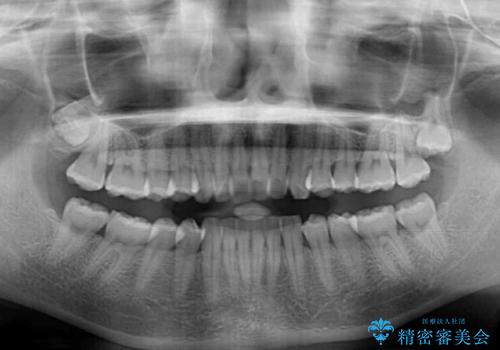

- 前歯の突出感を気にして来院された患者様です。

左右ともに奥歯の咬み合わせが上顎前突となっており、上顎前歯が飛び出している状態でした。

奥歯の咬み合わせ改善が必要であるため、マウスピース矯正より確実に達成のできるワイヤー矯正にて治療を行うこととしました。